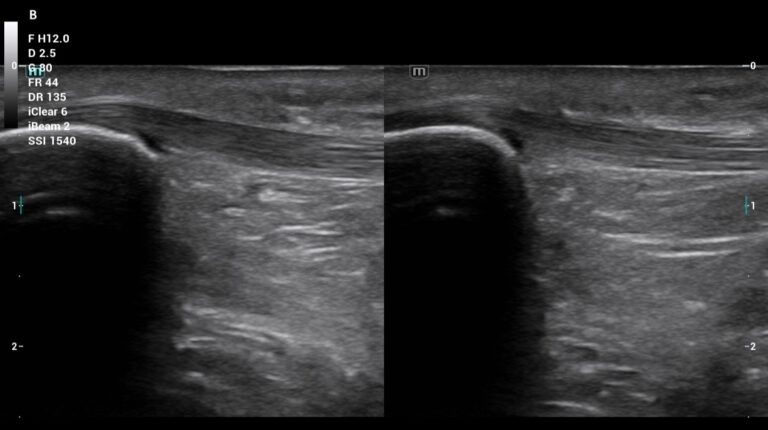

La ecografía musculoesquelética es una tecnología revolucionaria en el ámbito de la fisioterapia. Su capacidad para realizar un estudio dinámico, rápido, eficaz, inocuo y en tiempo real la convierte en una herramienta indispensable para la evaluación y diagnóstico fisioterapéutico, evaluando de forma objetiva el tejido neuromusculoesquelético y favoreciendo a la realización de un programa de tratamiento, totalmente personalizado.

La ecografía en fisioterapia no solo mejora la calidad del diagnóstico, sino que optimiza el tratamiento y aumenta la seguridad en intervenciones invasivas. Su capacidad para ofrecer un estudio comparativo en tiempo real marca un antes y un después en la atención fisioterapéutica, beneficiando tanto a los profesionales como a los pacientes.